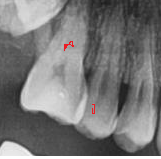

옆에 치아는 인접면 충치 있을 수도 있다고 하셔서 레진 예정이었는데요

현재 해당 사진으로 보아서는 특별히 충치가 심해보이거나 하지 않아 보입니다. 물론 현재 사진 하나로만 판단하기에는 무리가 있습니다. 파노라마 사진은 3차원적인 자료를 2차원으로 구현하기 때문에 보이지 않는 곳에 충치가 있을 수 있고 육안으로도 판단을 해야 합니다. 다만 두번째 치과에서 치료를 하지 않아도 된다면 하면 지금 상태에서 특별히 치료를 할 필요는 없어 보입니다.

눈으로 보이지 않는 부위의 충치는 촬영한 사진으로 확인할수 있는데 사진으로 아두운부위가 있다고 해서 무조건 충치가 있는 것은 아니에요

사진을 어떻게 분석했는에 따라서 치요계획에 차이가 있을수 있습니다

왜 크라운을 하셔야된다고는 못들으셧나요?엑스레이 사진상으로는 정확히 파악은 안되지만 크게 이상은 없어 보이긴합니다. 치아에 금이 갓거나 그런경우에는 크라운 치료를 하긴합니다.